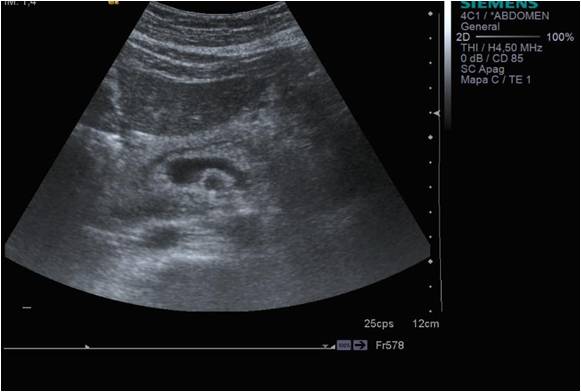

Se encuentra situado según la imagen anterior, posterior al Hígado y anterior a la aorta, pero lo que de verdad nos sirve de referencia para encontrar el órgano es una imagen en forma de renacuajo, anecoica y que en la imagen siguiente está silueteada en blanco.

Esta es la referencia más importante para encontrar el páncreas cuando lo estudiemos, encontrar esta estructura anecoica, que pasa justo posterior al órgano que lo acompaña y lo marca, que tiene forma de renacuajo y que es la Esplénica en su parte más delgada y la Porta en su parte más gruesa. Es sin duda la estructura que va a ayudarte, la aliada principal para encontrar ecográficamente el Páncreas.